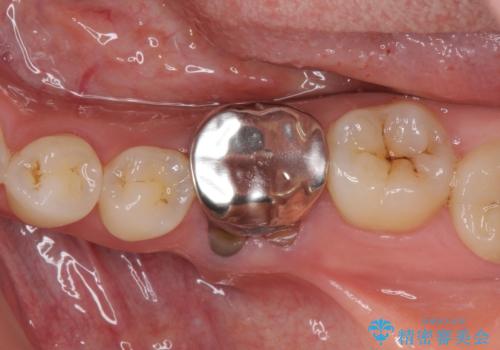

奥の銀歯も気になっていたため、矯正治療後にセラミッククラウンにて補綴することとしました。

- 天然歯を削ります

- 硬い素材は天然歯を傷つけてしまう場合があります

- かみ合わせや歯ぎしりが強すぎる方はセラミックが割れてしまう可能性があります

- 自費診療(保険適用外治療)となります